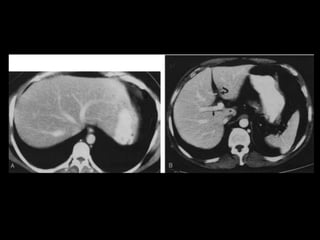

• TC: Tres fases

– Arterial (10 a 20 segundos)

– Fase venosa portal ( 30 segundos )

– Fase venosa hepática (60 segundos)

• TC Portografia: Metastases.

Técnicas de Imagem •US: Primeiro exame pedido ao: 1) dor no hipocondrio direito; 2) testes de função hepáticas anormais; 3) suspeita de malignidade. • TC: Tres fases – Arterial (10 a 20 segundos) – Fase venosa portal ( 30 segundos ) – Fase venosa hepática (60 segundos) • TC Portografia: Metastases.